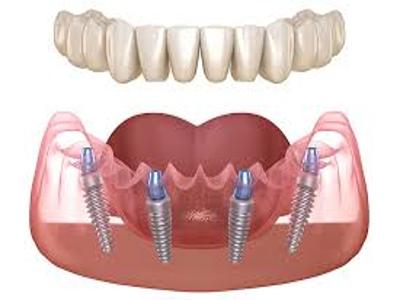

Elevate your dental care journey with our membership program, specifically designed for patients seeking teeth implants. As a member, you’ll benefit from reduced pricing on implant procedures, priority scheduling for consultations and treatments, and continuous follow-up care to ensure the best outcomes. Join today to access top-tier dental implant services and enhance your smile with confidence.